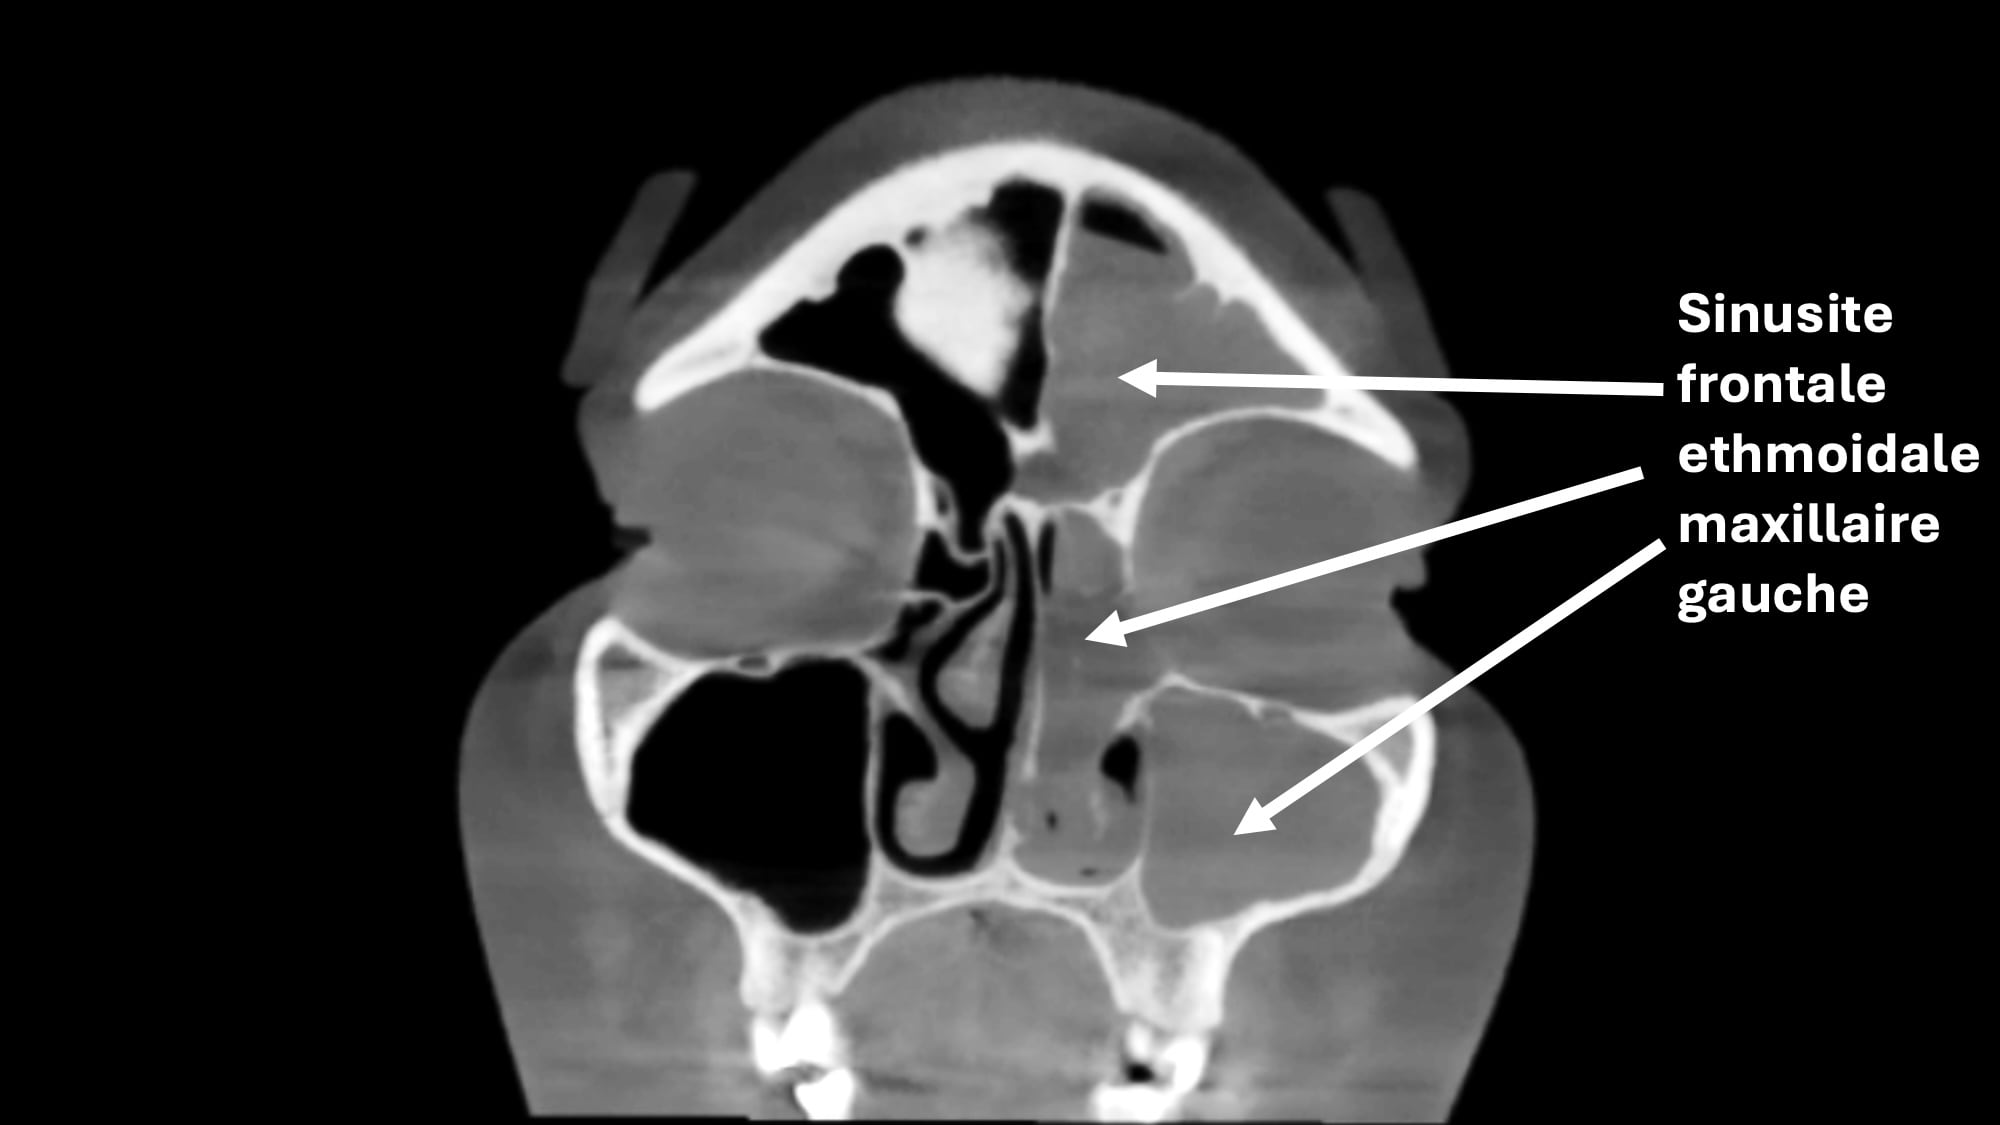

Sinusite chronique

La sinusite chronique est une inflammation persistante des sinus, qui dure plus de 12 semaines.

Symptômes : On retrouve un nez bouché, des douleurs faciales, un écoulement nasal purulent ou clair, et/ou une perte partielle ou totale de l’odorat.

Traitement : Il repose sur les lavages de nez avec du sérum physiologique, les sprays à base de cortisone, les antibiotiques en cas de surinfection, et les antihistaminiques si une composante allergique est présente. Un traitement antibiotique au long terme (3 mois) peut être proposé dans certains cas. Si les symptômes persistent malgré le traitement médical bien mené, une chirurgie endonasale (par les narines, sans cicatrice visible) peut être proposée